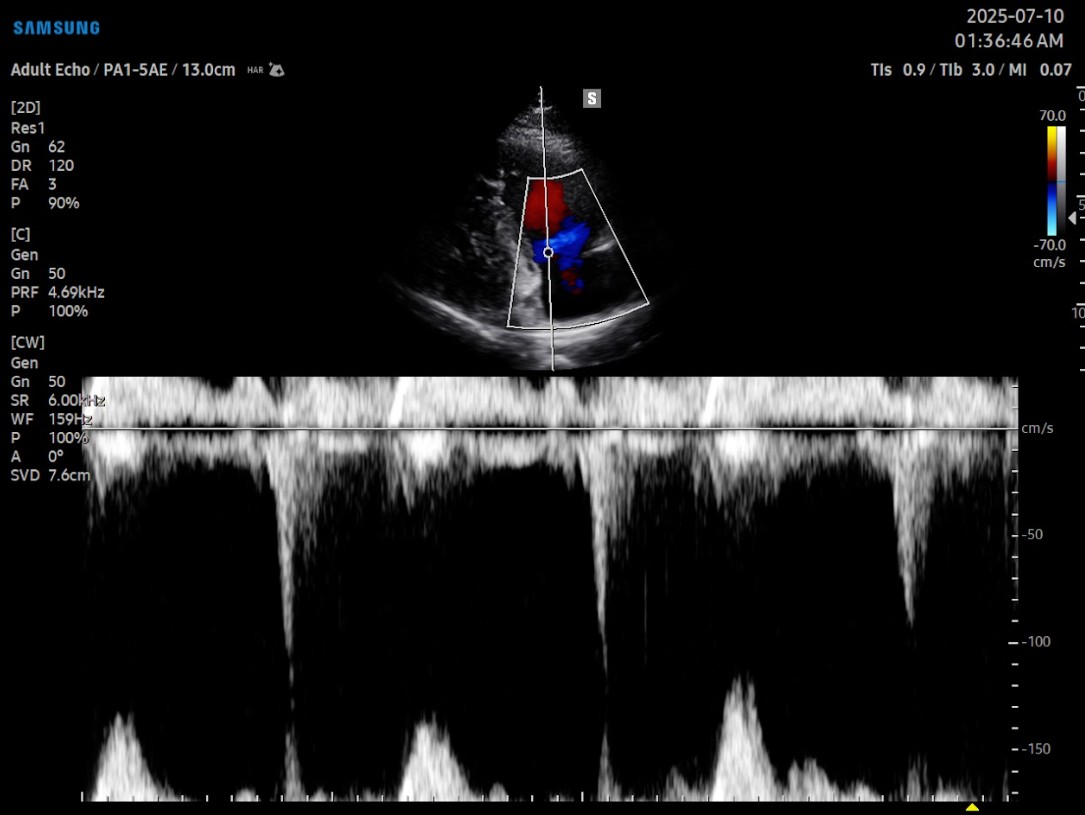

Gracias a su arquitectura Crystal™ (CrystalBeam™ y CrystalLive™), el cV6 entrega imágenes 2D y Doppler con gran claridad y resolución, lo que permite visualizar estructuras vasculares finas, flujos lentos y movimiento miocárdico con un nivel de detalle excepcional.Tecnologías como MV-Flow™, LumiFlow™, ClearVision y S-Flow™ optimizan la detección de microvasculatura y realzan el contraste sin sacrificar velocidad, siendo especialmente útiles en estudios cardiacos, vasculares y pediátricos.

En el ámbito cardiológico, el V6 incorpora herramientas avanzadas como HeartAssist™, que reconoce automáticamente las principales vistas cardíacas y facilita la orientación del operador. También incluye Strain+™, AutoEF™, StressEcho, y ArterialAnalysis™, que permiten evaluar la deformación ventricular, la fracción de eyección y la rigidez arterial de forma automatizada, estandarizando los resultados entre operadores y reduciendo los tiempos de exploración.